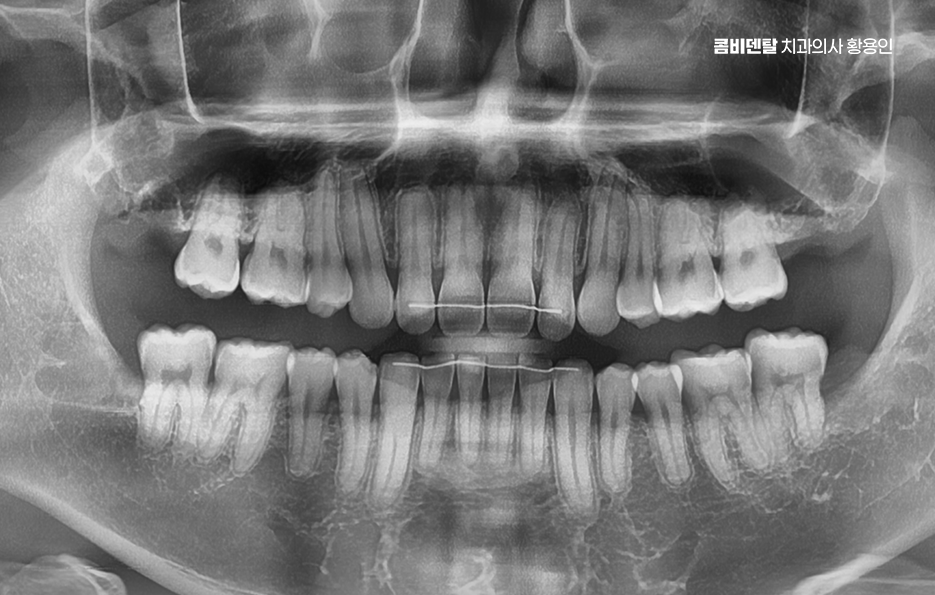

출처 아카이브 열기완전매복사랑니라는 단어 자체가 참 낯설게 느껴졌어요, 처음에는 그게 무슨 말인지조차 몰랐고, 단순히 사랑니라는 건 그냥 어금니 맨 끝에 나중에 나오는 이 정도로만 알고 있었어요 누구나 한 번쯤은 뽑는 거니까 나한테도 언젠간 그런 일이 생기겠지 하면서도, 사실 딱히 깊이 고민해본 적은 없었어요, 그런데 어느 날 왼쪽 아래 턱 깊숙한 곳이 묘하게 욱신거리고, 무언가 불편한 느낌이 계속되더라고요, 딱히 부어오르거나 겉으로 드러난 문제는 아닌데, 먹을 때마다 이상하게 한쪽으로는 씹기 싫고, 가만히 있을 때도 잇몸 깊은 곳에서 묵직한 압력이 느껴지는 기분이었어요, 그게 몇 주째 반복되니까 이제는 그냥 넘길 수 없겠다는 생각이 들어서 치과에 가게 됐어요. 진료를 받고, 엑스레이를 찍고, 설명을 듣는데, 그제야 알게 된 게 바로 완전매복사랑니라는 이름이었어요, 내 사랑니는 겉으로는 전혀 드러나지 않았지만, 잇몸과 뼈 안쪽 깊숙이 누운 채로 누워 있었고, 그것도 똑바로 난 게 아니라 옆 어금니 방향을 향해 비스듬히 자라고 있다는 것이었죠. 문제는 사랑니 발치도 까다로울 수 있고 주변 치아나 잇몸에도 영향을 줄 수 있다는 점이었어요

완전 매복사랑니는 말 그대로 잇몸 속에 완전히 묻혀 있는 사랑니를 말하며 겉으로 보이질 않기 때문에 문제가 없는 것처럼 느껴지기도 하지만 실제로는 겉으로 안 보인다는 이유만으로 안심할 수 없으며 오히려 잇몸 속 깊숙이 들어가 있기 때문에 문제가 생겼을 때 더 큰 통증이나 합병증으로 이어질 수 있는 게 바로 완전 매복사랑니의 특징이라 할 수 있었어요

완전 매복사랑니는 보통 아래턱, 즉 하악의 뒤쪽에서 자주 발견되는데 위턱보다는 아래턱 뼈가 더 단단하고 구조적으로 복잡해서 발치 난이도가 더 높을 수 있으며 이 매복된 사랑니는 위치나 각도에 따라서도 발치의 난이도가 달라질 수 있었어요

매복된 사랑니는 겉으로 보이지 않기 때문에 대부분의 경우 증상이 없다고 생각하기 쉬운데 매복된 사랑니 주변은 세균이 쉽게 모이고 염증이 생기기 쉬운 구조로서 완전히 뼈 속에 묻혀 있어도 턱 안쪽에서 염증 반응이 시작되면 얼굴 붓기, 통증, 구취, 심할 경우 턱관절이나 림프절까지 부어오르는 일이 생길 수 있어요.

여기에 더해서 신경과의 거리도 문제로 아래턱에는 하치조신경이라는 굵은 감각신경이 지나가는데 완전 매복사랑니의 뿌리가 이 신경과 가까이 위치해 있는 경우가 많아서 만약 발치 중 이 신경을 건드리거나 손상이 생기면, 입술이나 턱 끝 부위에 감각 이상이 생길 수 있어요.

완전매복사랑니 발치 그래서 무조건 바로 뽑는다고 되는 게 아니라, 사전에 정밀한 진단과 영상검사가 꼭 필요하며 일반적인 파노라마 사진 외에도 CT 촬영을 통해 신경과의 거리, 뿌리의 형태, 턱뼈의 두께 등을 정밀하게 확인해야 발치 계획을 안전하게 세울 수 있었어요.